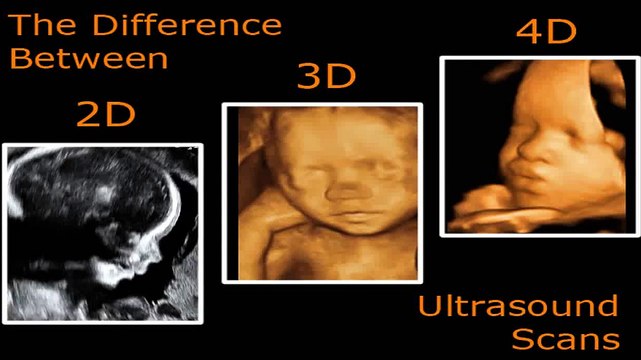

You would like to rearrange for prepare ultrasound, Toronto ultrasound scan may well be a medical ensure uses high-frequency sound waves to capture live photos from the at intervals of your body